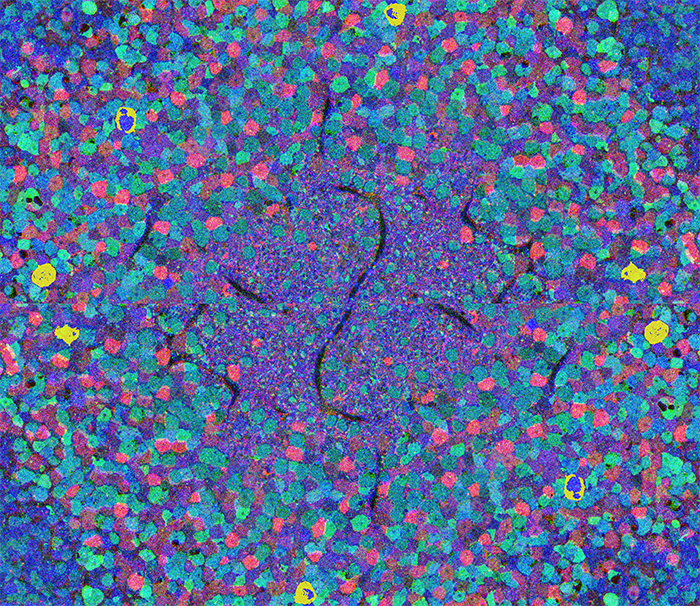

Metabolic Kaleidoscope